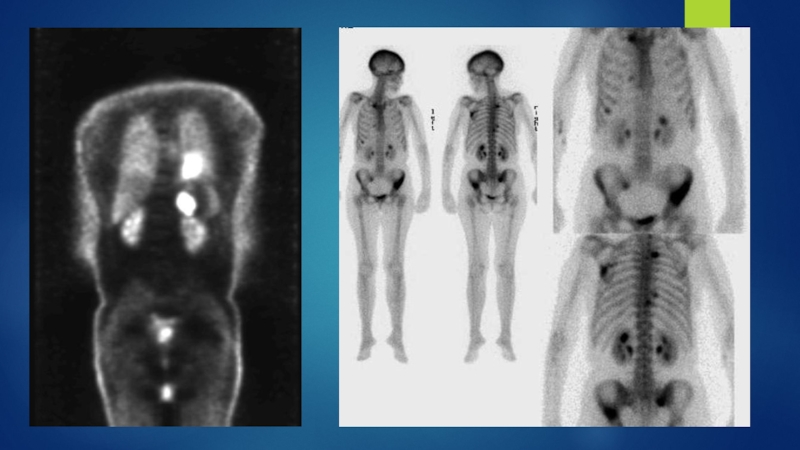

С целью определения степени распространенности процесса производят: КТ органов грудной

полости и верхнего этажа брюшной полости (печень, надпочечники), КТ с контрастированием, МРТ, ПЭТ/КТ, сцинтиграфия костей, КТ или МРТ головного мозга.

ДиагностикаСбор жалоб, анамнез.Данные объективного исследования.Рентгенография:инфильтрат в легкомрасширение средостеньяателектазплевральный выпотБронхоскопияЦитологическое исследование мокротыС целью определения степени распространенности процесса производят: